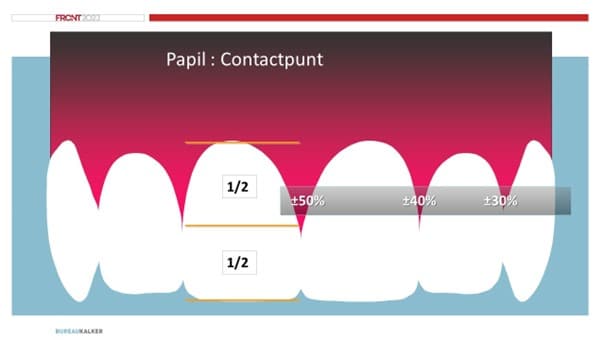

TWES-scores

0 = geen slijtage

1 = slijtage alleen in het glazuur

2 = slijtage tot in het dentine, klinische kroonhoogte <1/3e

3 = slijtage tot in het dentine, klinische kroonhoogte >1/3e, maar < 2/3e

4 = slijtage tot in dentine, klinische kroonhoogte >2/3e

TWES ernst

0 = geen

1 = mild

2 = matig

3 = ernstig

4 = extreem